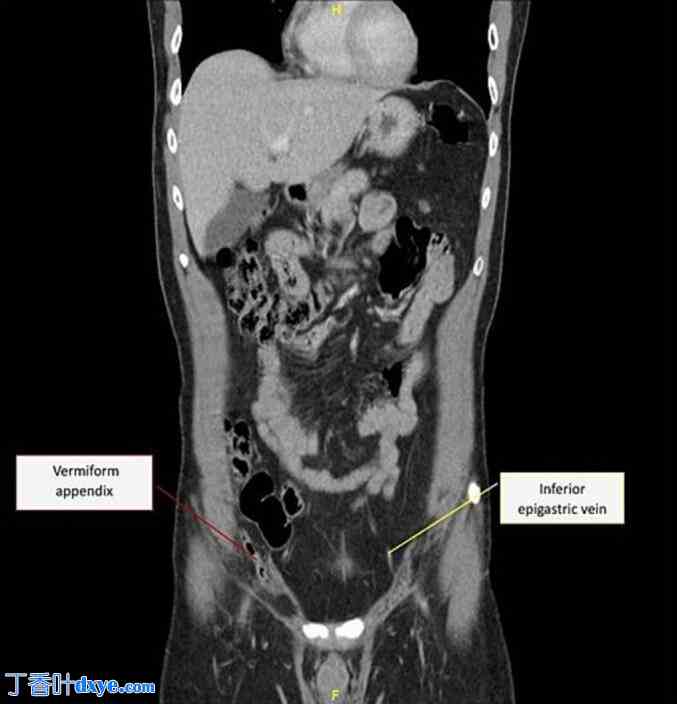

腹部和盆腔CT扫描证实右侧腹股沟疝,疝内容物为脂肪和阑尾尖端。疝囊颈长约1厘米,阑尾长约0.6厘米。此外,还意外发现T10椎体呈蝶形畸形,并可能存在脾囊肿,但这些在临床上被认为意义不大(图1.1)。放射学诊断为Amyand疝,并制定了择期手术修复方案。

图1.1

腹部CT冠状位图像显示疝出的阑尾(红色标签)。